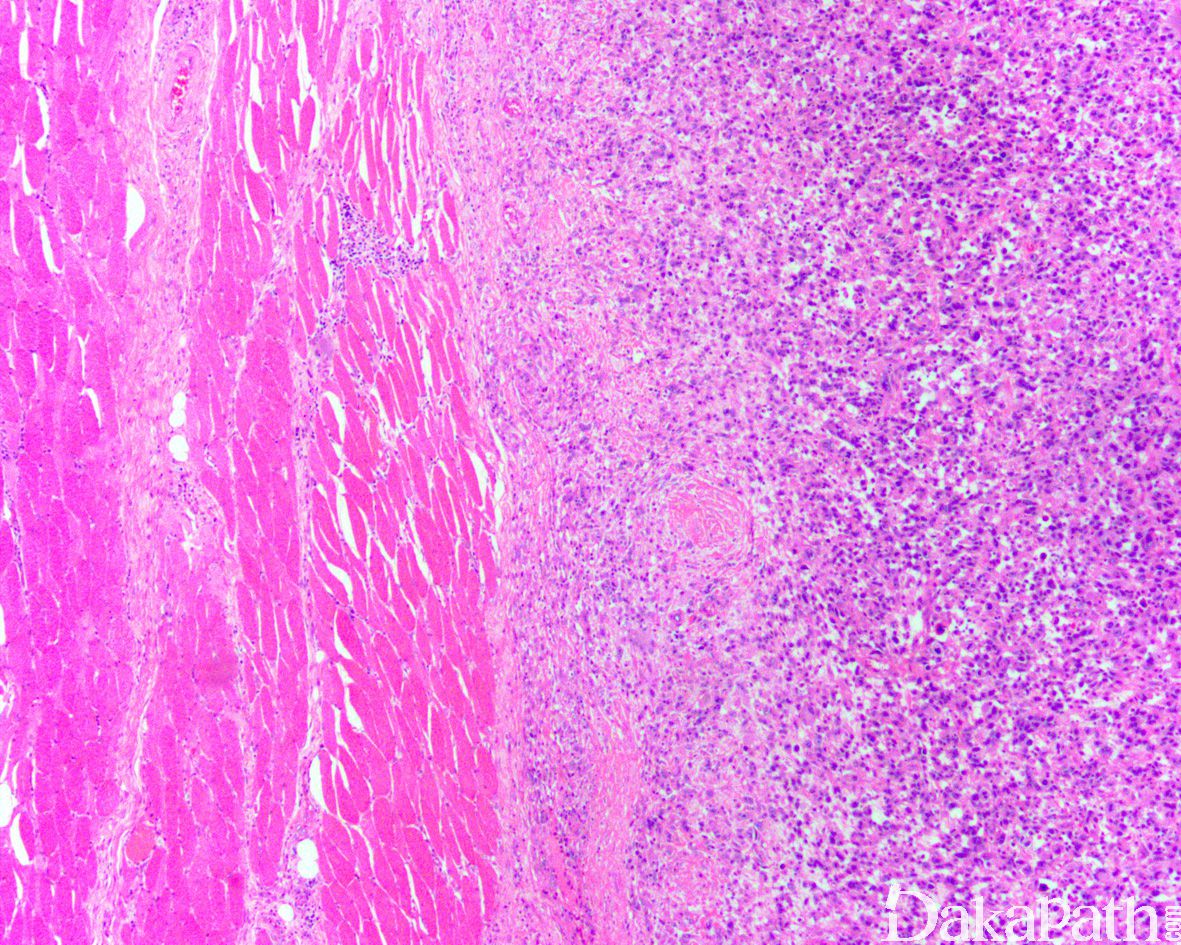

发病部位: 好发于肢体深部软组织,尤其是大腿

多发生于 45 岁以上的中老年人,偶可发生于儿童,常见于下肢,尤其是大腿,肿瘤界限相对清楚;

有些病例见梭形细胞呈束状或不规则状排列,偶尔可呈席纹状排列;部分病例还可见血管外皮瘤样排列;